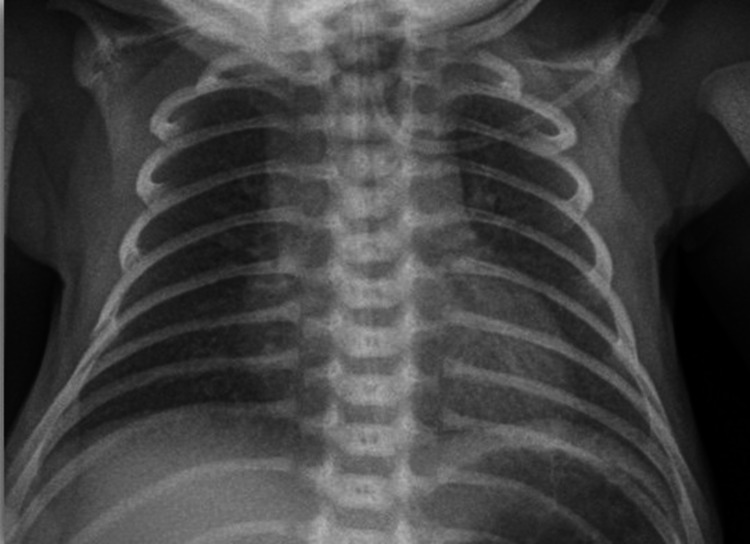

Picture 5.

Grade 1—X ray

On plain X-ray radiography, there is reticulogranular or ground-glass opacification, progressive hypoaeration, and air bronchograms [11].

Radiographic findings were classified into four stages, from mild to severe disease [10] Table 2 and Pictures 5, 6, 7, 8.